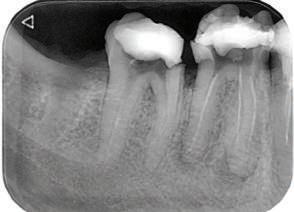

орални снимки и снимки на позата, пал пация на мускулите, брукс-чекър, оклу зограми, кондилография, рентгеногра фии, СВСТ и ядрено-магнитен резонанс на темпоромандибуларните стави). Преди началото на ортодонтското лечение всички стари възстановява ния бяха свалени и бяха заменени с дъл госрочни временни от хибридна керами ка. На девитализираните зъби бе прове дено ендодонтско релечение. Индивиду ализиран оклузален сплинт бе направен с цел да се постигне контролирано репо зициониране на долната челюст, като носенето му продължи три месеца до възстановяване на правилната позиция на ставния диск и затихване на орофаци алната болка и дискомфорт в ставата. Брекетите в горната челюст бяха за лепени, за да започне подреждането и нивелирането на зъбите, докато паци ентът все още носеше сплинта. След края на терапията със сплинта бе на правена кондилография, за да се потвър ди триизмерната позиция на долната челюст. След залепване на брекетите в долна

тация на долната челюст. Дъга GUMMETAL с tip-back извивки бе поставена в долната челюст за ниве лиране кривата на Шпее. Случаят бе финализиран с 19x25 SS дъги в горната и долната зъбна дъга за координиране. Преди да се изготви финалният восъ чен моделаж, естетичните и лицеви те характеристики бяха анализирани с помощта на дигитален дизайн на ус мивката, за да се създаде мок-ъп, чии то форма и размери да бъдат одобрени от пациента. Бе оценена фонетиката и бяха заснети лицеви снимки и видеа. Зъ бите бяха изпилени, като препарация та бе изцяло водена от функционалния восъчен моделаж, прехвърлен в устата на пациента. След препарацията восъч ният моделаж бе напаснат и насложен върху препарационния модел и бе фрезо ван от e-max multi bl 1. Циментирането на финалните конструкции бе направе но при изолация с кофердам, следвайки адхезивния протокол. След циментирането бе направено проследяване на оклузията чрез снема не на отпечатъци, монтиране на моде лите в артикулатор в окончателната интеркуспидация и внимателно прове ряване за наличие на блокажи при воде ни движения.